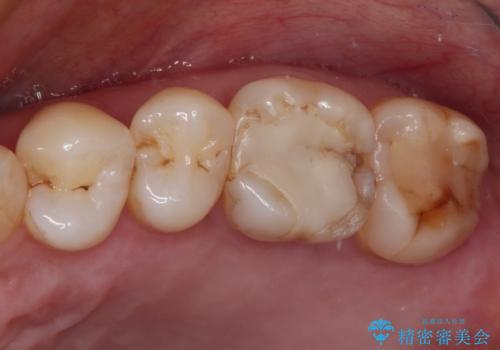

放置した虫歯 根管治療とオールセラミッククラウン